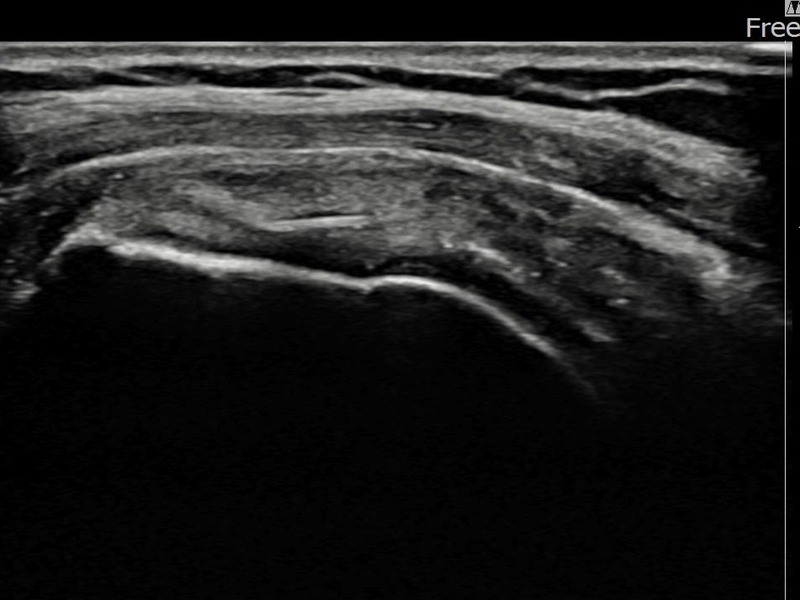

정ㅇㅇ님 · 좌측 극상근건 부분파열

좌측 어깨 통증이 오래 지속되어 내원하셨습니다. 초음파 검사에서 극상근건 부분파열이 확인되었으며, 어깨인대 축소봉합술 시행 후 장기 추적 초음파에서 힘줄 연속성이 완전히 회복된 것이 확인되었습니다.